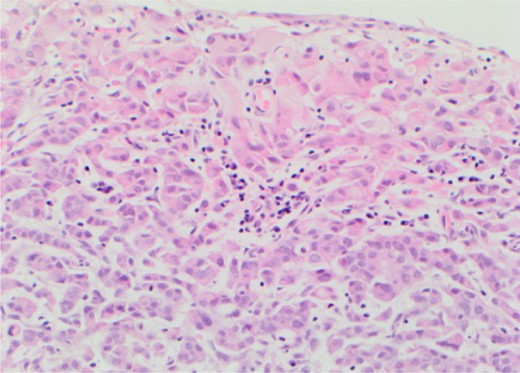

Metastatic lobular carcinoma of the breast identified on right wall of bladder.

The histopathological analysis identified two distinct malignant entities. The solid tumour at the base of bladder was confirmed as muscle invasive bladder cancer (G3pT2) whilst the satellite lesion showed features suggestive of metastatic lobular carcinoma of the breast. Following discussion at both urological and breast MDTs palliative chemotherapy was administered to address the metastatic breast cancer whilst palliative radiotherapy was used to contain the primary bladder cancer.